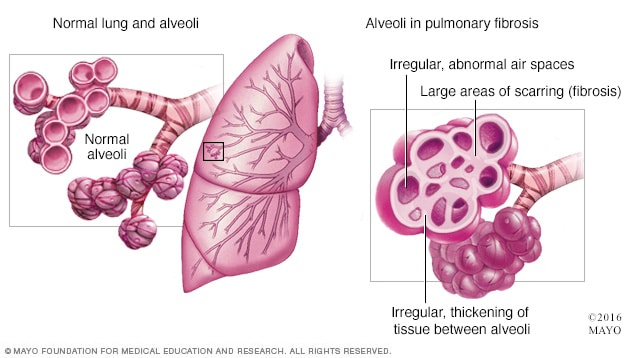

La fibrosis pulmonar idiopática es una enfermedad progresiva en la que se van produciendo cicatrices en ambos pulmones que dificultan el intercambio de oxígeno y provocan tos crónica y disnea o falta de aire.

La sustitución cicatricial del tejido normal de pulmón provoca disminución irreversible de la capacidad de difusión de oxígeno (oxigenación).[3] Por otra parte, la disminución de la distensibilidad pulmonar por fibrosis conforma una enfermedad pulmonar restrictiva. La genética puede desempeñar un papel en la causa de la fibrosis pulmonar.[19] Si más de un miembro de una familia tiene fibrosis pulmonar, la enfermedad se llama fibrosis pulmonar familiar.[19] La fibrosis pulmonar puede no tener causa conocida, en cuyo caso se denomina fibrosis pulmonar idiopática, o puede ser causada por un gran número de variables, en cuyo caso suele remitir al eliminar el factor desencadenante.

¿Y cuáles son los principales síntomas de la fibrosis pulmonar idiopática? Según este neumólogo, los primeros signos son la fatiga y ahogo al realizar un esfuerzo (disnea), la tos seca e irritativa, los cambios en las uñas de manos y pies o dedos de palillo de tambor (acropaquia), los sonidos crepitantes al respirar (similares al ruido que produce el velcro) y, por último, el pulmón en panel de abeja, es decir, cuando el órgano pierde su forma habitual y adopta una estructura parecida a un panal. Este acto también ha contado con la participación de la Asociación de Familiares y Enfermos de Fibrosis Pulmonar Idiopática (Afefpi) y la Federación Española de Enfermedades Raras (Feder), así como la colaboración de los laboratorios Boehringer.

La fibrosis pulmonar es una enfermedad pulmonar intersticial caracterizada por la sustitución de tejido pulmonar por tejido colágeno.